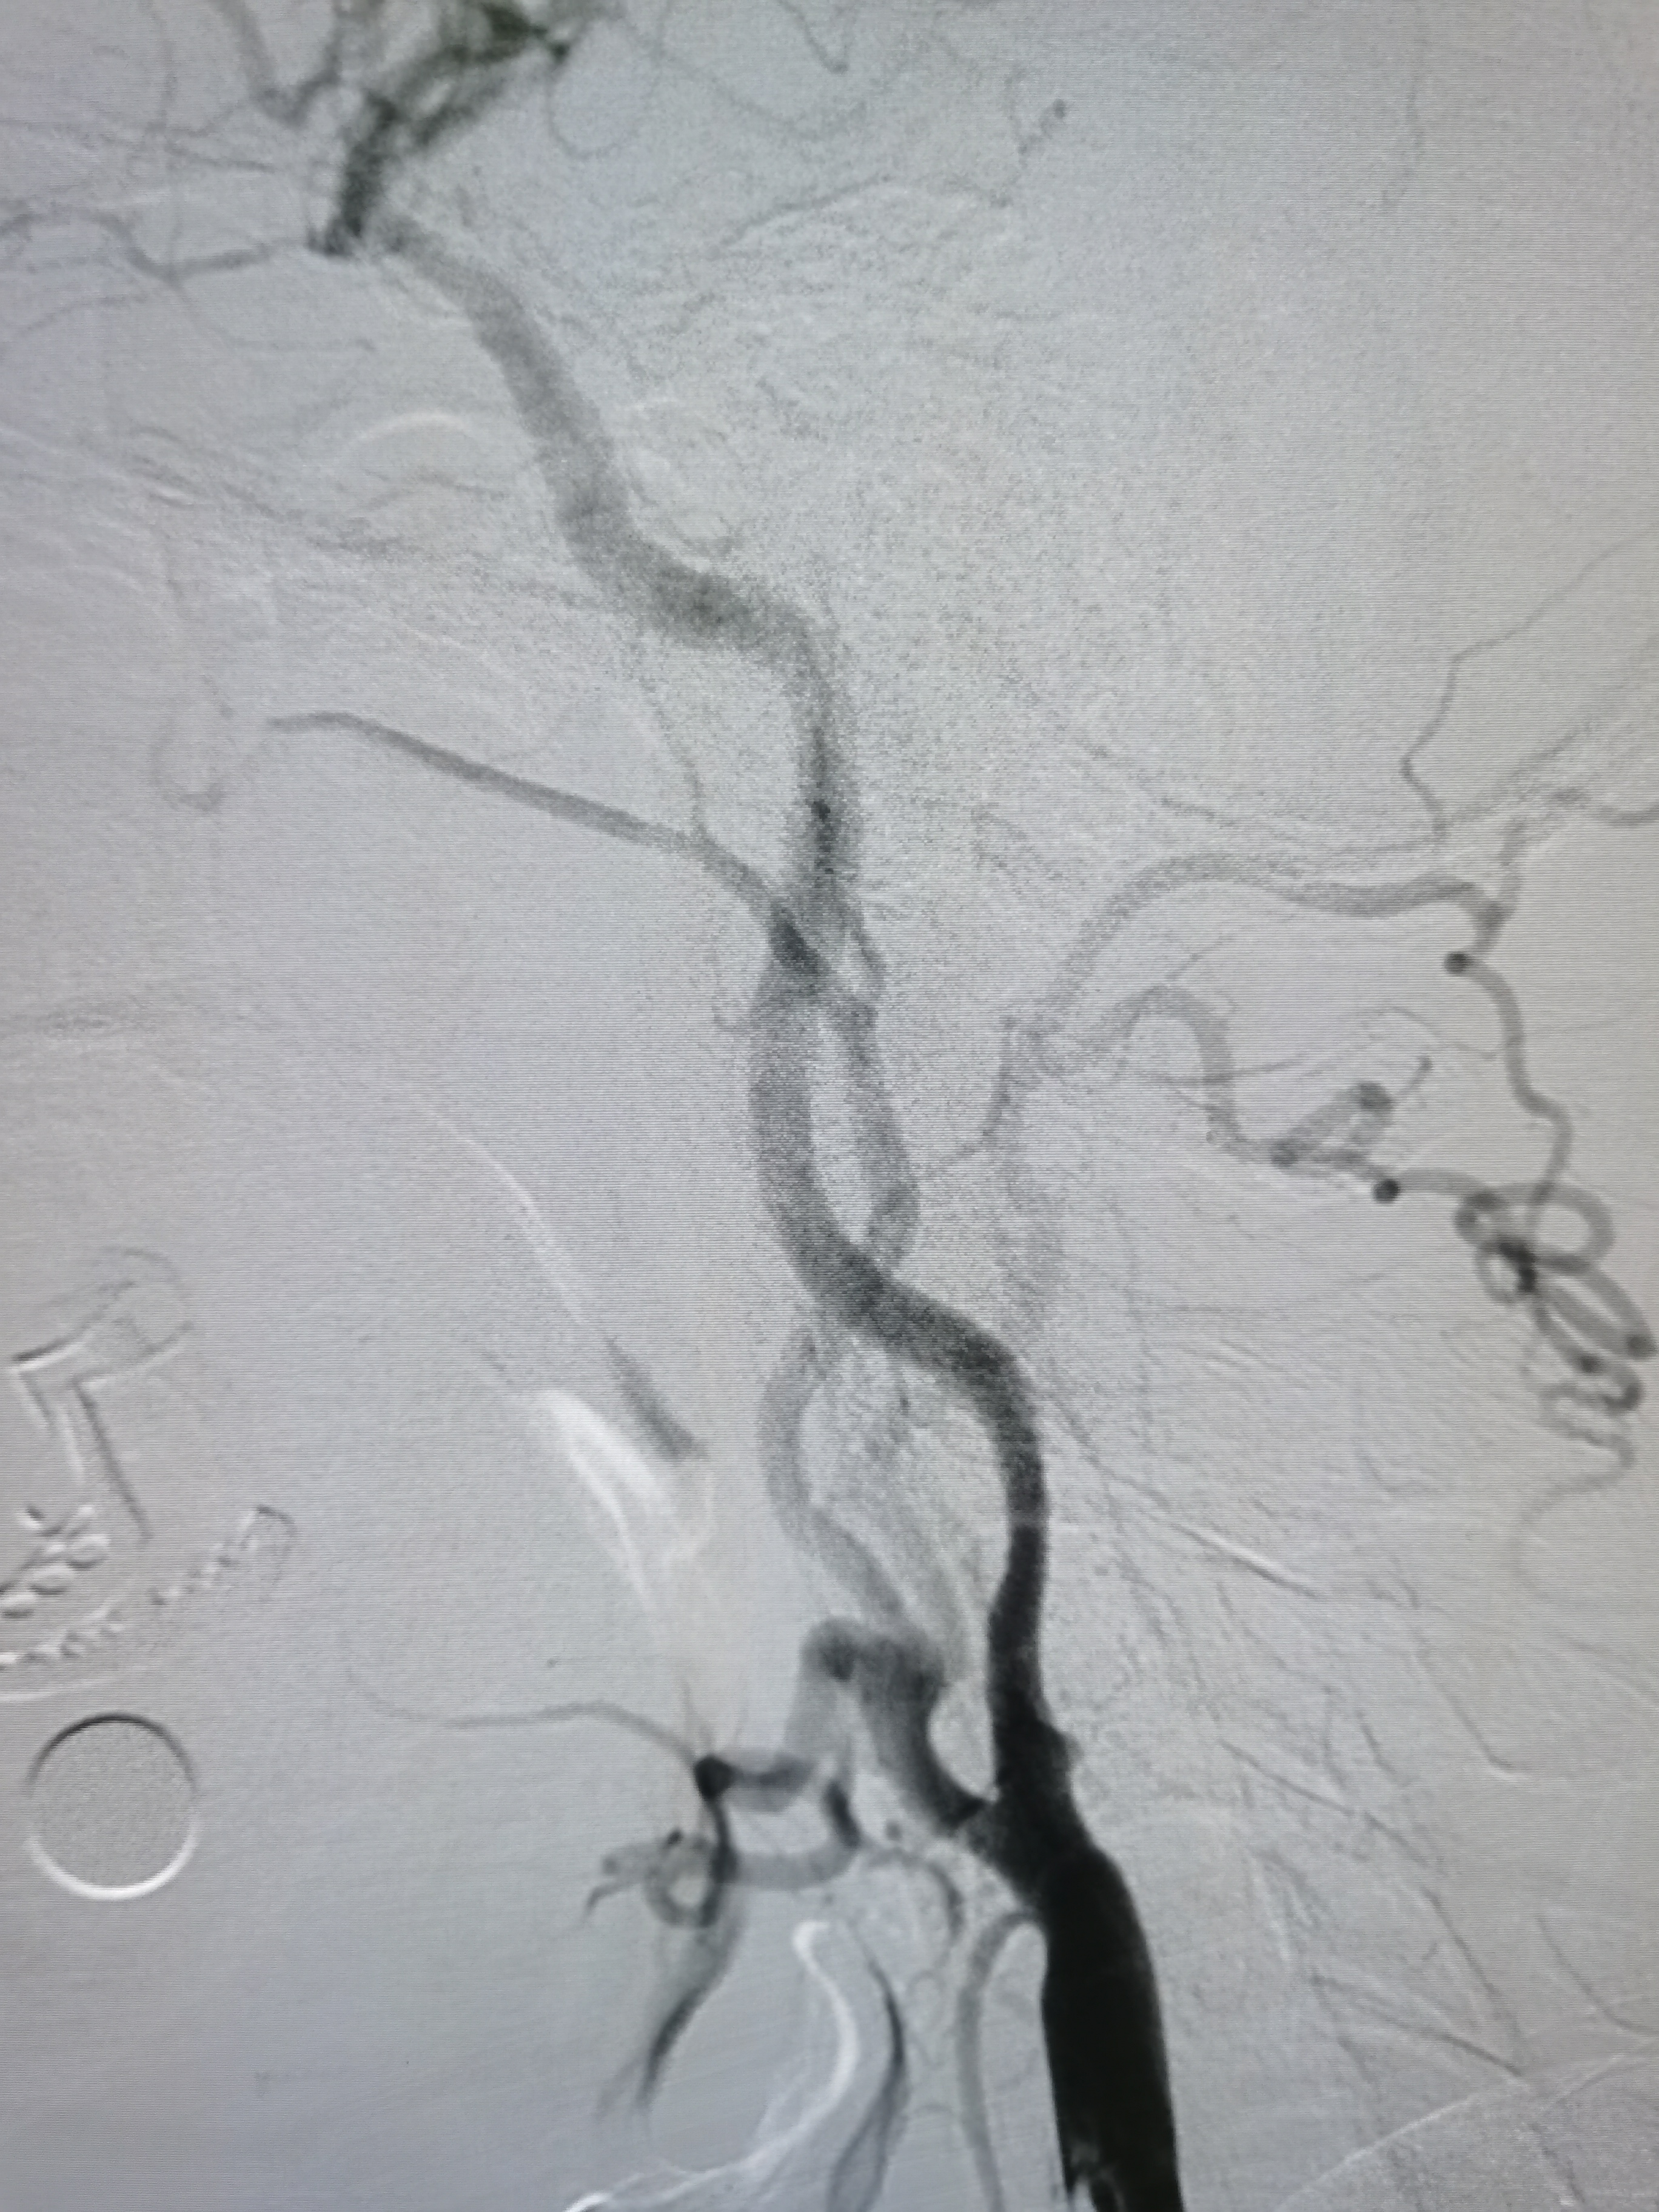

将导引导管调至右侧颈总末端,送入远端保护伞,4/30球囊预扩。

7-9/40支架定位

支架释放后狭窄改善,考虑患者高龄,颅内动脉硬化,担心术后高灌注出血,遂未再进行大球囊后扩。

撤出保护伞,造影见狭窄改善明显。

术前术后对比